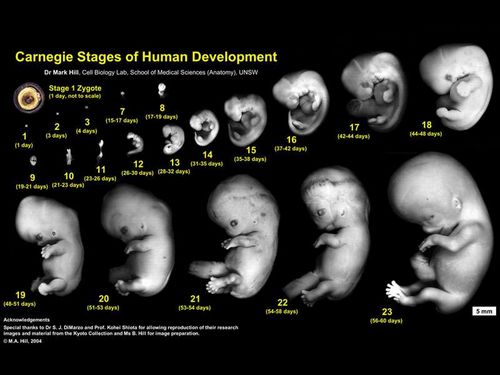

Глобально періоди вагітності поділяють на:

- ембріональний, або зародковий період вагітності - до 10 тижнів акушерського терміну. Цей період включає момент запліднення, коли зародок має в розмірі всього лише 0,1 мм. Далі відбувається активне зростання і розвиток ембріона. В ембріональний період вагітності майбутній малюк більше нагадує крихітну земноводних рибку, ніж чоловічка. Все чари починається на наступному етапі вагітності!

- фетальний, або плодовий період вагітності. До початку плодового етапу вагітності ембріон вже має всі сформовані системи і позбувся зябрових щілин, хвоста і інших земноводних оранів. Майбутній малюк починає дуже активно рости і все швидше перетворюється на людину!

Також періоди вагітності прийнято розділяти на триместри, яких всього ТРИ!

Найбільш небезпечним і ризикованим вважається перший триместр вагітності, коли дитина ще існує у вигляді декількох клітинок або зародка. У цей період ризик викидня в 10 разів вище, ніж в наступні періоди вагітності.Періоди вагітності. вагітність по тижнях, вагітність в картинках.

Перший триместр вагітності. 4 тижні вагітності.

Це, звичайно, ембріональний період розвитку, коли малюк ще не схожий на немовля. До 4 тижні вагітності зародок має розмір кількох міліметрів. Формується голова, хребет, є серце і система кровообігу. При УЗ дослідженні вже видно кровоносні судини. У майбутньої дитини вже є мозок!

Перший триместр вагітності. 6 тижнів вагітності.

На 6 тижні вагітності під всю формується мозок і нервова система. Це видно по початковій рефлекторної активності зародка. У ембріона чітко видно ручки і ніжки з крихітними пальчиками, вушка, очки і носик. Формується печінку, легені і шлунок. Серце стає 4-х камерним.

Перший триместр вагітності. 8 тиждень вагітності.

Це стадія вагітності, коли у зародка вже є всі найважливіші органи. Формуються м'язи, скелет. На даному етапі вагітності йде активне вдосконалення нервової системи і інших основних систем організму.

Перший триместр вагітності. 10 тиждень вагітності.

З цього етапу вагітності починається чарівництво. малюк вже рухається в животі у мами. Тільки ці рухи дуже слабкі і мама їх не відчуває. Організм дитини стає все більш досконалим: з'являються нігті на пальцях рук і ніг, органи і системи вже досить складні і розвинені. В даний період вагітності стетоскопом можна прослухати серцебиття малюка!

Перший триместр вагітності. 12 тиждень вагітності.

Ембріон вже настільки розвинений, що починає виробляти кров всередині кісток, нирки виробляють сечу, малюк ковтає. На очках видно повіки. М'язи і скелет вже цілком розвинені і рухи дитини більш явні і повноцінні.